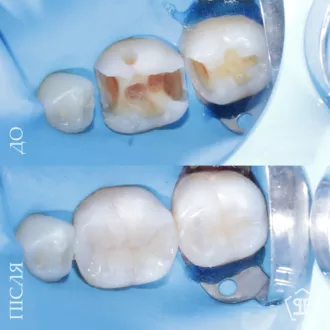

Пациент обратился с жалобами на повышенную чувствительность к воздуху и сладкую пищу в области угловых зубов. После обследования и диагностического разбора КТ был диагностирован глубокий контактный кариес 14 и 15 зуба. Произведено изолирование зубов кофердамом, с последующим раскрытием кариозных полостей и последующим восстановлением утраченных тканей методом художественной реставрации.